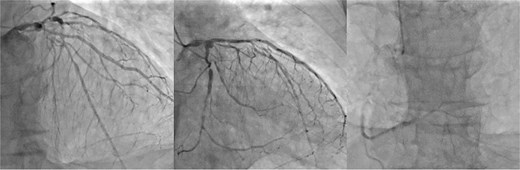

A 77-year-old man with chronic kidney disease was admitted to another hospital with heart failure and was diagnosed with IHD and triple vessel disease (Fig. 1). On examination, femoral pulses were absent, and angiography revealed occlusion of the abdominal aorta below the renal arteries. Therefore, he was transferred to our hospital for further management. Heart failure was stabilized with medical therapy, and semi-urgent surgery was planned. Because he had no symptoms in the lower extremities, elective performance of revascularization of the lower limbs was scheduled. The ITAs served as important collateral vessels to the lower limbs (Fig. 2); therefore, their use as grafts was considered a risk factor for lower limb ischemia. Transthoracic echocardiography revealed impaired systolic function with an ejection fraction of 42%, whereas contrast-enhanced computed tomography (CT) demonstrated diffuse calcification of the ascending aorta (porcelain aorta). However, an area near the origin of the brachiocephalic artery was considered suitable for arterial cannulation, and a proximal site above the fat band was identified as appropriate for saphenous vein graft (SVG) anastomosis (Fig. 3). Based on these findings, an on-pump total venous CABG strategy was selected, and surgery was performed on the second day after transfer.

Preoperative coronary angiography. Preoperative coronary angiography image showing severe triple-vessel disease.